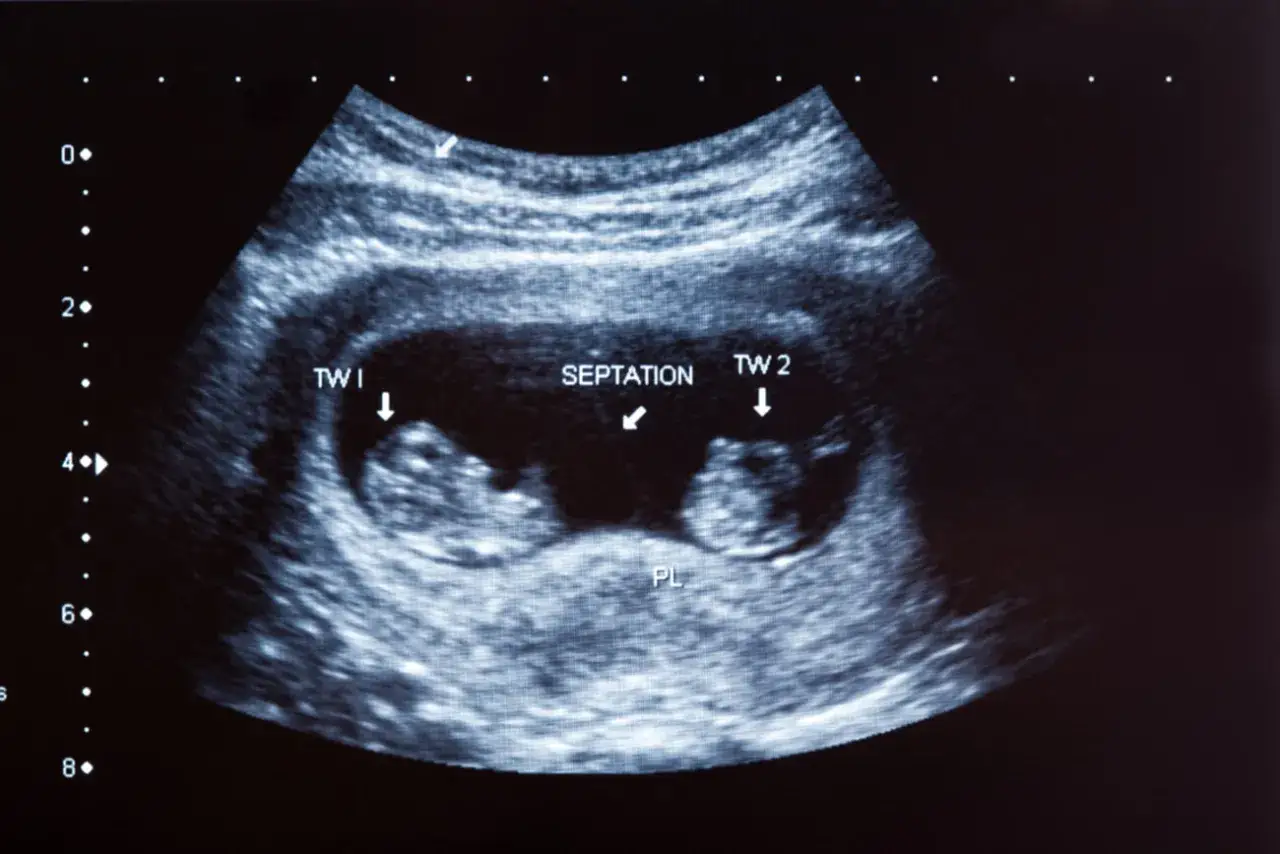

Badanie USG to klucz do wczesnego rozpoznania ciąży bliźniaczej. Ciążę dwukosmówkową, czyli taką, w której każdy płód ma swój worek owodniowy i łożysko, można uwidocznić w badaniu USG już w 4. tygodniu. Ciążę jednokosmówkową, gdzie płody dzielą łożysko, można zauważyć tydzień później, około 5. tygodnia. Jednak stuprocentową pewność uzyskujemy zazwyczaj między 6. a 8. tygodniem ciąży, kiedy to wyraźnie widoczne są już zarodki z bijącymi sercami. To właśnie ten moment, kiedy przyszli rodzice często po raz pierwszy słyszą podwójne bicie serca i zdają sobie sprawę z podwójnego szczęścia.

Warto pamiętać, że choć widoczne dwa pęcherzyki ciążowe są silną wskazówką, pełną gwarancję bliźniąt daje dopiero uwidocznienie dwóch zarodków z bijącymi sercami w późniejszym etapie wczesnej ciąży. Czasami jeden z pęcherzyków może być pusty lub rozwój jednego z zarodków może ustać, dlatego zawsze czekamy na ten kluczowy moment z bijącymi sercami.

Na wczesnym etapie diagnostyki USG może być trudniej ostatecznie potwierdzić ciążę bliźniaczą. Małe rozmiary struktur, możliwe nakładanie się obrazów czy indywidualne różnice w rozwoju mogą sprawić, że lekarz będzie potrzebował kilku dni lub tygodnia na ponowne badanie, aby zyskać pełną pewność. Dlatego też, choć pierwsze sygnały mogą pojawić się wcześnie, ostateczną diagnozę stawiamy zazwyczaj około 6-8. tygodnia, kiedy obraz jest już znacznie bardziej klarowny.